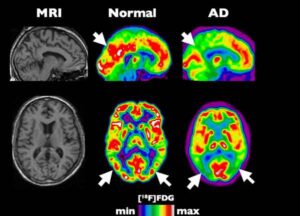

Gli scienziati alzano la posta. Contro le malattie del cervello bisogna giocare d'anticipo. In altre parole diagnosi precoce: il tema portante...